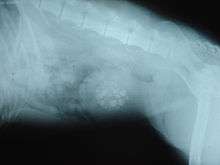

Diagnosis

When symptoms indicate bladder stones, the first step is usually to take an x-ray. Most types of stones will appear readily in an x-ray, urate and occasionally cystine stones being the most common exceptions. Stones smaller than three millimeters may not be visible.[3] Ultrasonography is also useful for identifying bladder stones. Crystals identified in a urinalysis may help identify the stones, but analysis of the stones is necessary for identification of the complete chemical composition.